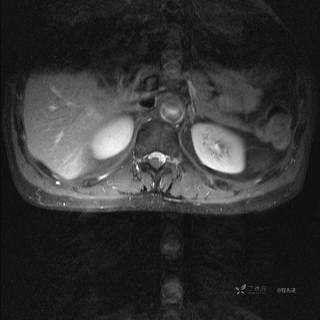

MR

T2

T2压脂

T1

T1增强

T1增强冠状位

T1增强横断位